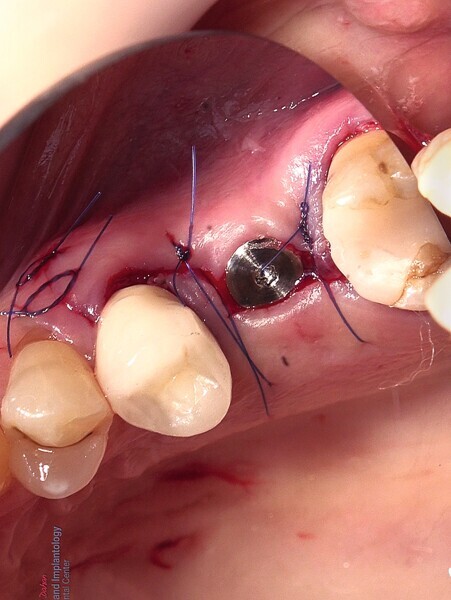

Fig. 20 : Mise en place d’une membrane de collagène et suture.

Fig. 21 : Mise en place d’une membrane de collagène et suture.

Fig. 22 : Mise en place d’une membrane de collagène et suture.

La pose immédiate d’un implant deux pièces en céramique au niveau tissulaire a été accomplie tout en préservant l’alvéole (allogreffe constituée d’un substitut osseux et protection par une membrane de collagène résorbable). La mise en charge n’a pas été réalisée à ce stade (Figs. 12–24)